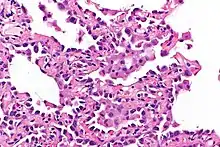

Micrograph showing multifocal micronodular pneumocyte hyperplasia. H&E stain.

• Well-demarcated, nodular lesions ranging 2–5 mm in pulmonary parenchyma.

• Type II pneumocytes without nuclear atypia lined thickened alveolar septa and proliferated papillary structures.

• Enlarged cuboidal cells lining mildly thickened alveolar septa.[11]

• Enlarged cuboidal cells have abundant, eosinophilic cytoplasm and large, round nuclei.[12]

• Papillary pattern with irregular margin and lymphocyte infiltration in the stroma.[13]

• No proliferation of immature smooth muscle cells suggestive of lymphangioleiomyomatosis.